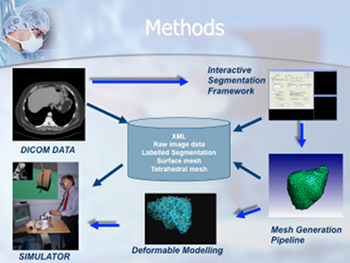

P. F. Villard, F. P. Vidal, L. ap Cenydd, R. Holbrey, S. Pisharody,

S. Johnson, A. Bulpitt, N. W. John, F. Bello, and D. Gould.

Interventional radiology virtual simulator for liver biopsy.

International Journal of Computer Assisted Radiology and

Surgery, 9(2):255-267, March 2014.

Purpose: Training in Interventional Radiology currently uses the apprenticeship model, where clinical and technical skills of invasive procedures are learnt during practice in patients. This apprenticeship training method is increasingly limited by regulatory restrictions on working hours, concerns over patient risk through trainees’ inexperience and the variable exposure to case mix and emergencies during training. To address this, we have developed a computer-based simulation of visceral needle puncture procedures. Methods: A real-time framework has been built that includes: segmentation, physically based modelling, haptics rendering, pseudo-ultrasound generation and the concept of a physical mannequin. It is the result of a close collaboration between different universities, involving computer scientists, clinicians, clinical engineers and occupational psychologists. Results: The technical implementation of the framework is a robust and real-time simulation environment combining a physical platform and an immersive computerized virtual environment. The face, content and construct validation have been previously assessed, showing the reliability and effectiveness of this framework, as well as its potential for teaching visceral needle puncture. Conclusion: A simulator for ultrasound-guided liver biopsy has been developed. It includes functionalities and metrics extracted from cognitive task analysis. This framework can be useful during training, particularly given the known difficulties in gaining significant practice of core skills in patients. Keywords: Biomedical computing, Image segmentation, Simulation, Virtual reality |